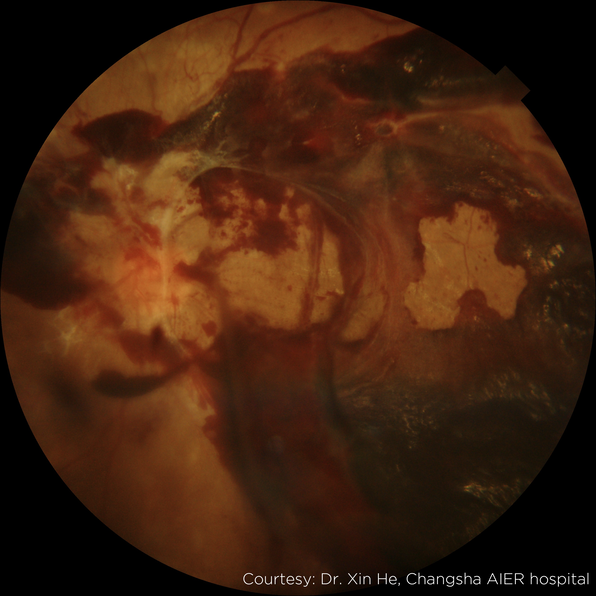

Image Gallery